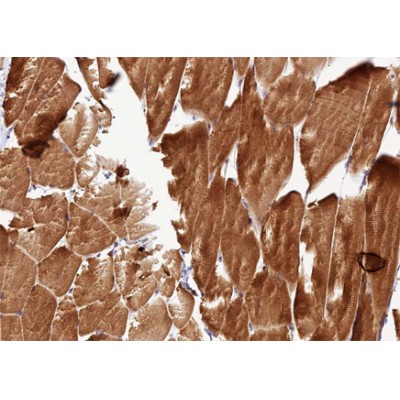

ab11143 at 1/200 staining human Skeletal muscle tissue sections by IHC-P. The tissue was formaldehyde fixed and a heat mediated antigen retrieval step in citrate buffer was performed. The tissue was then blocked and incubated with the antibody for 1.5 hours at 22°C. An HRP conjugated goat anti-rabbit antibody was used as the secondary antibody....